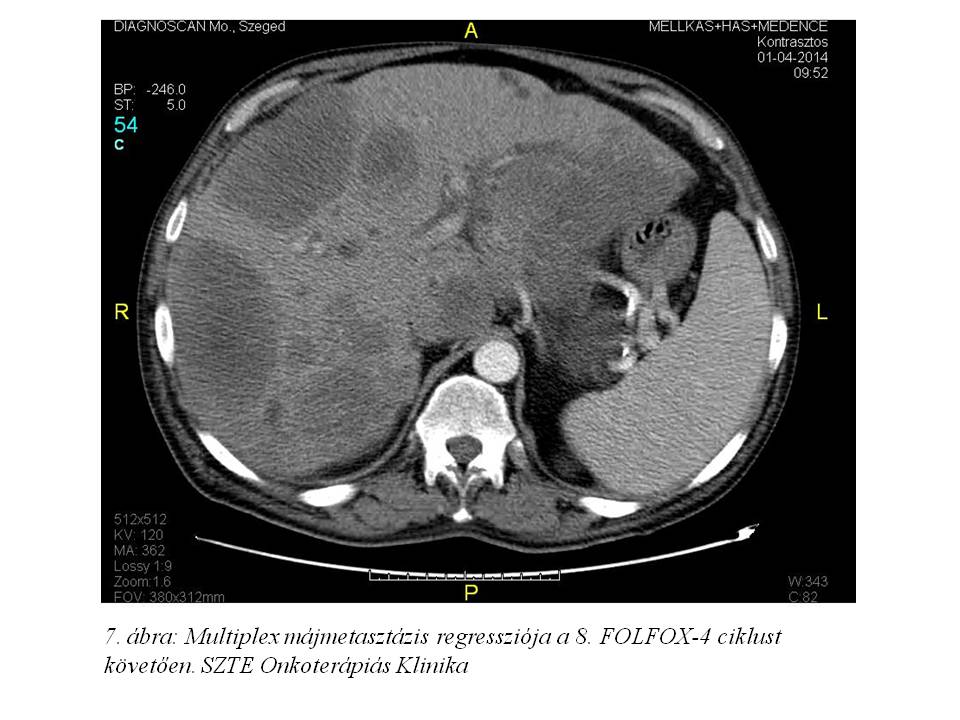

A 8. ciklust követő soros re-staging mellkas, has-kismedence CT-n további regressziót láttunk (2014.04.01., 7. ábra, 8. ábra); a CA 19-9: 27.9 U/ml (normalizálódott), a CEA: 258 ng/ml (megfeleződött). A 9. ciklusra érkezésekor említette először a tenyerek-talpak fokozott hidegérzetét, ekkor még zsibbadás nem volt (oxaliplatin okozta mellékhatásként ismert perifériás sensoros neuropathia). Az oxaliplatin dózisában 1. szintű redukciót alkalmaztunk (75 mg/m2).